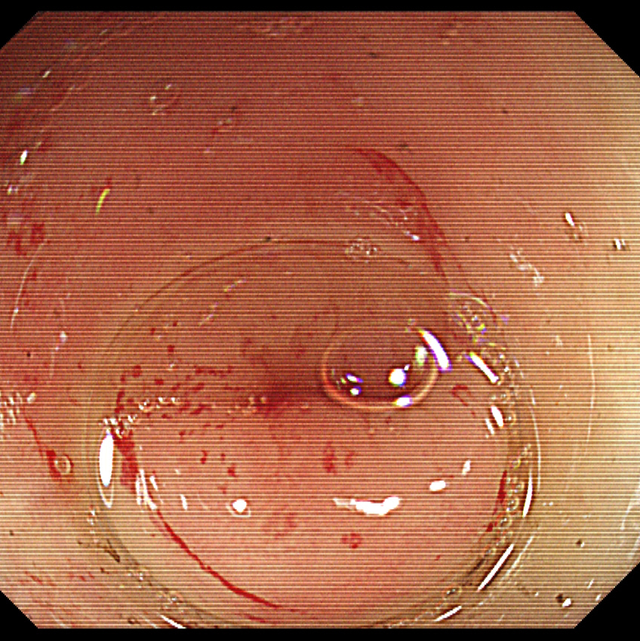

术中利用无痛肠镜技术到达阑尾开口,采用最新的“eyeMAX洞察”子母镜系统直视下进入阑尾腔内,通过冲洗、引流、网篮套取等操作,将嵌顿于阑尾腔内的粪石取出,术后患者腹痛明显缓解,1h后即可下地行走。次日顺利出院。

据徐宏伟主任介绍:内镜下逆行性阑尾炎治疗术是一种新型的内镜技术,经肠镜达到阑尾开口处,通过子母镜系统将超细的内镜探头置入阑尾腔内,直视下观察阑尾内部情况,并通过相关的器械(导管、网篮、支架等)对阑尾内的脓液、粪石进行处理,解除阑尾的梗阻,清除阑尾的炎症,是阑尾炎治疗的一种新型方式,相比外科手术而言,有着以下三大特点: